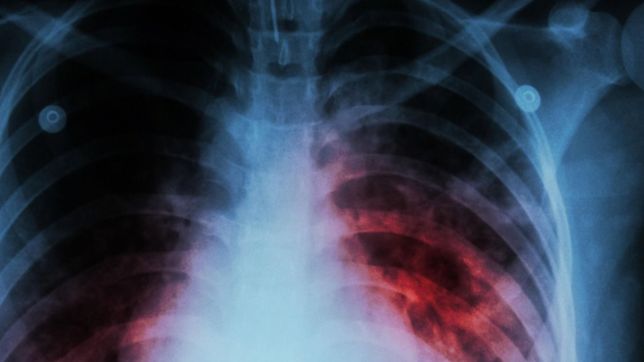

PREOCUPACIÓN Y CUIDADOS Alerta y medidas de control en una escuela de la región por un caso de tuberculosis